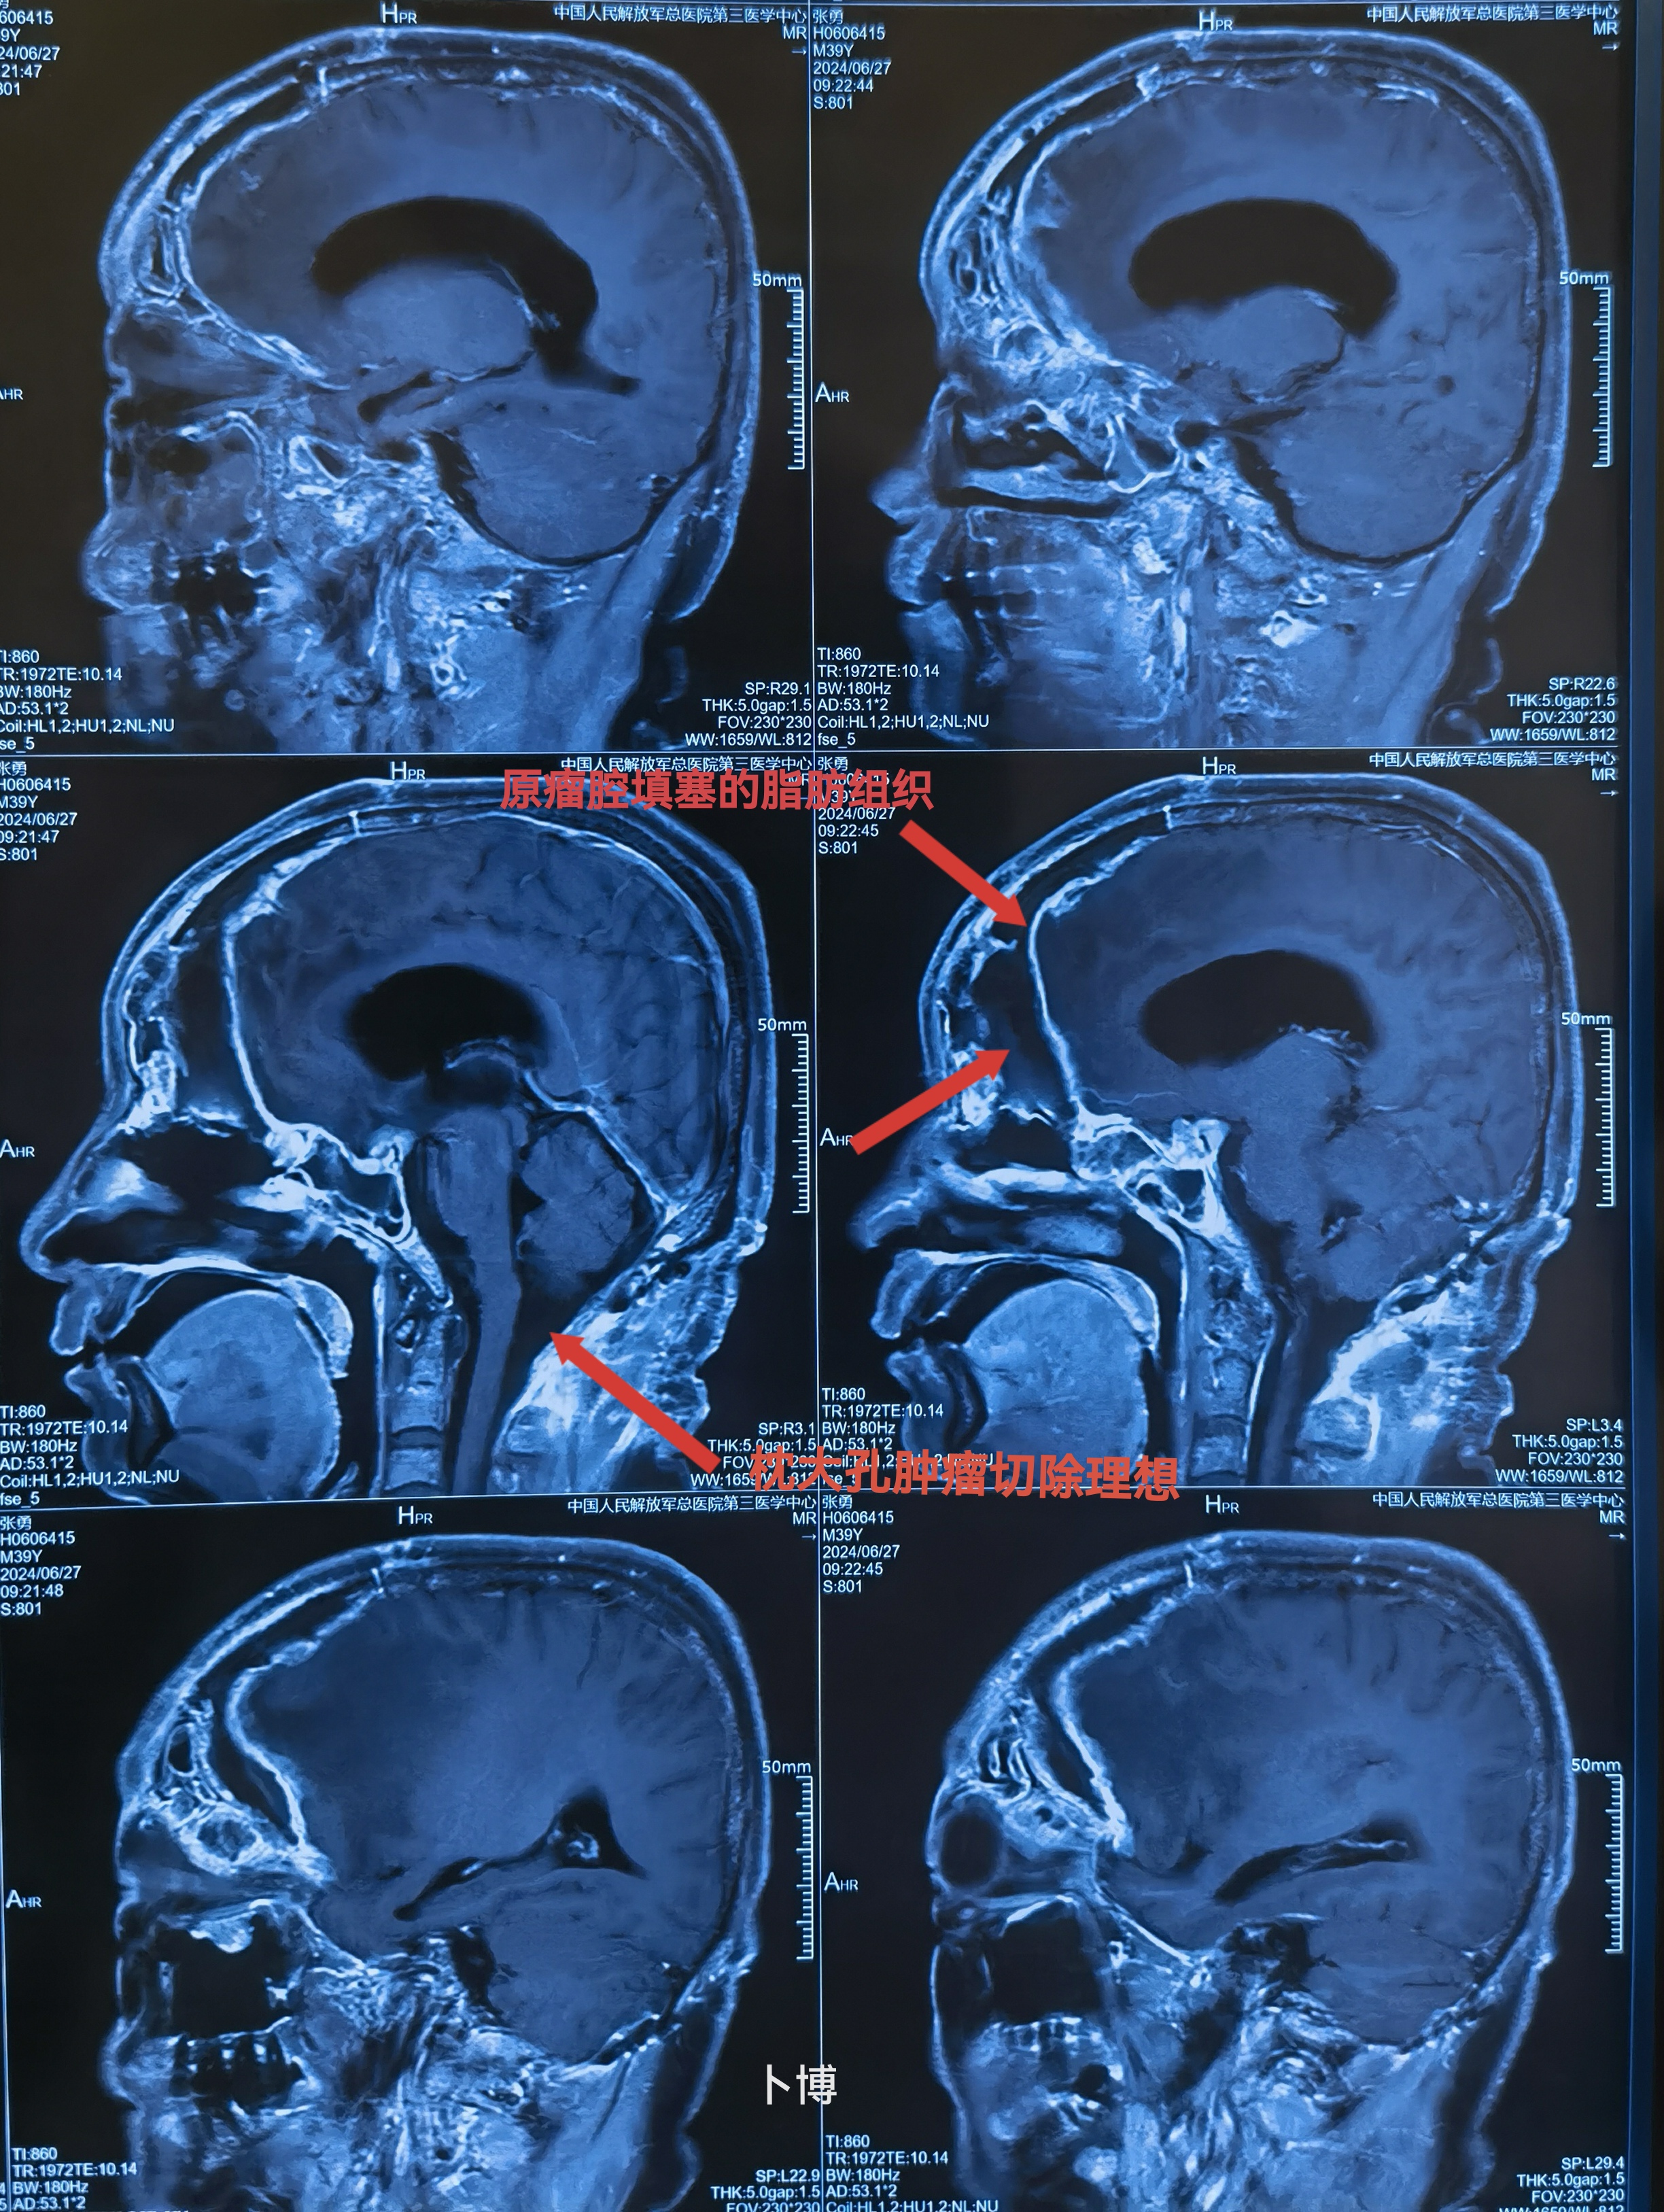

MRI可见肿瘤巨大,中鼻道以上,蝶窦筛窦及双侧额底均为肿瘤组织占据,向两侧到蝶骨嵴。肿瘤分叶状,可明显增强,核心区有坏死。后部可见粗大的静脉。双侧大脑前动脉位于肿瘤的后部。

枕大孔区种植转移,挤压脑干。已于6周前切除。

肿瘤向后到鞍结节前床突,向外到两侧的蝶骨嵴。

术后复查,提示切除理想。颅内的低密度改变为脂肪组织。

术后一个半月,肿瘤切除理想。

术后一个半月,肿瘤切除理想。既往未做放疗,建议做全脑加局部伽马刀。